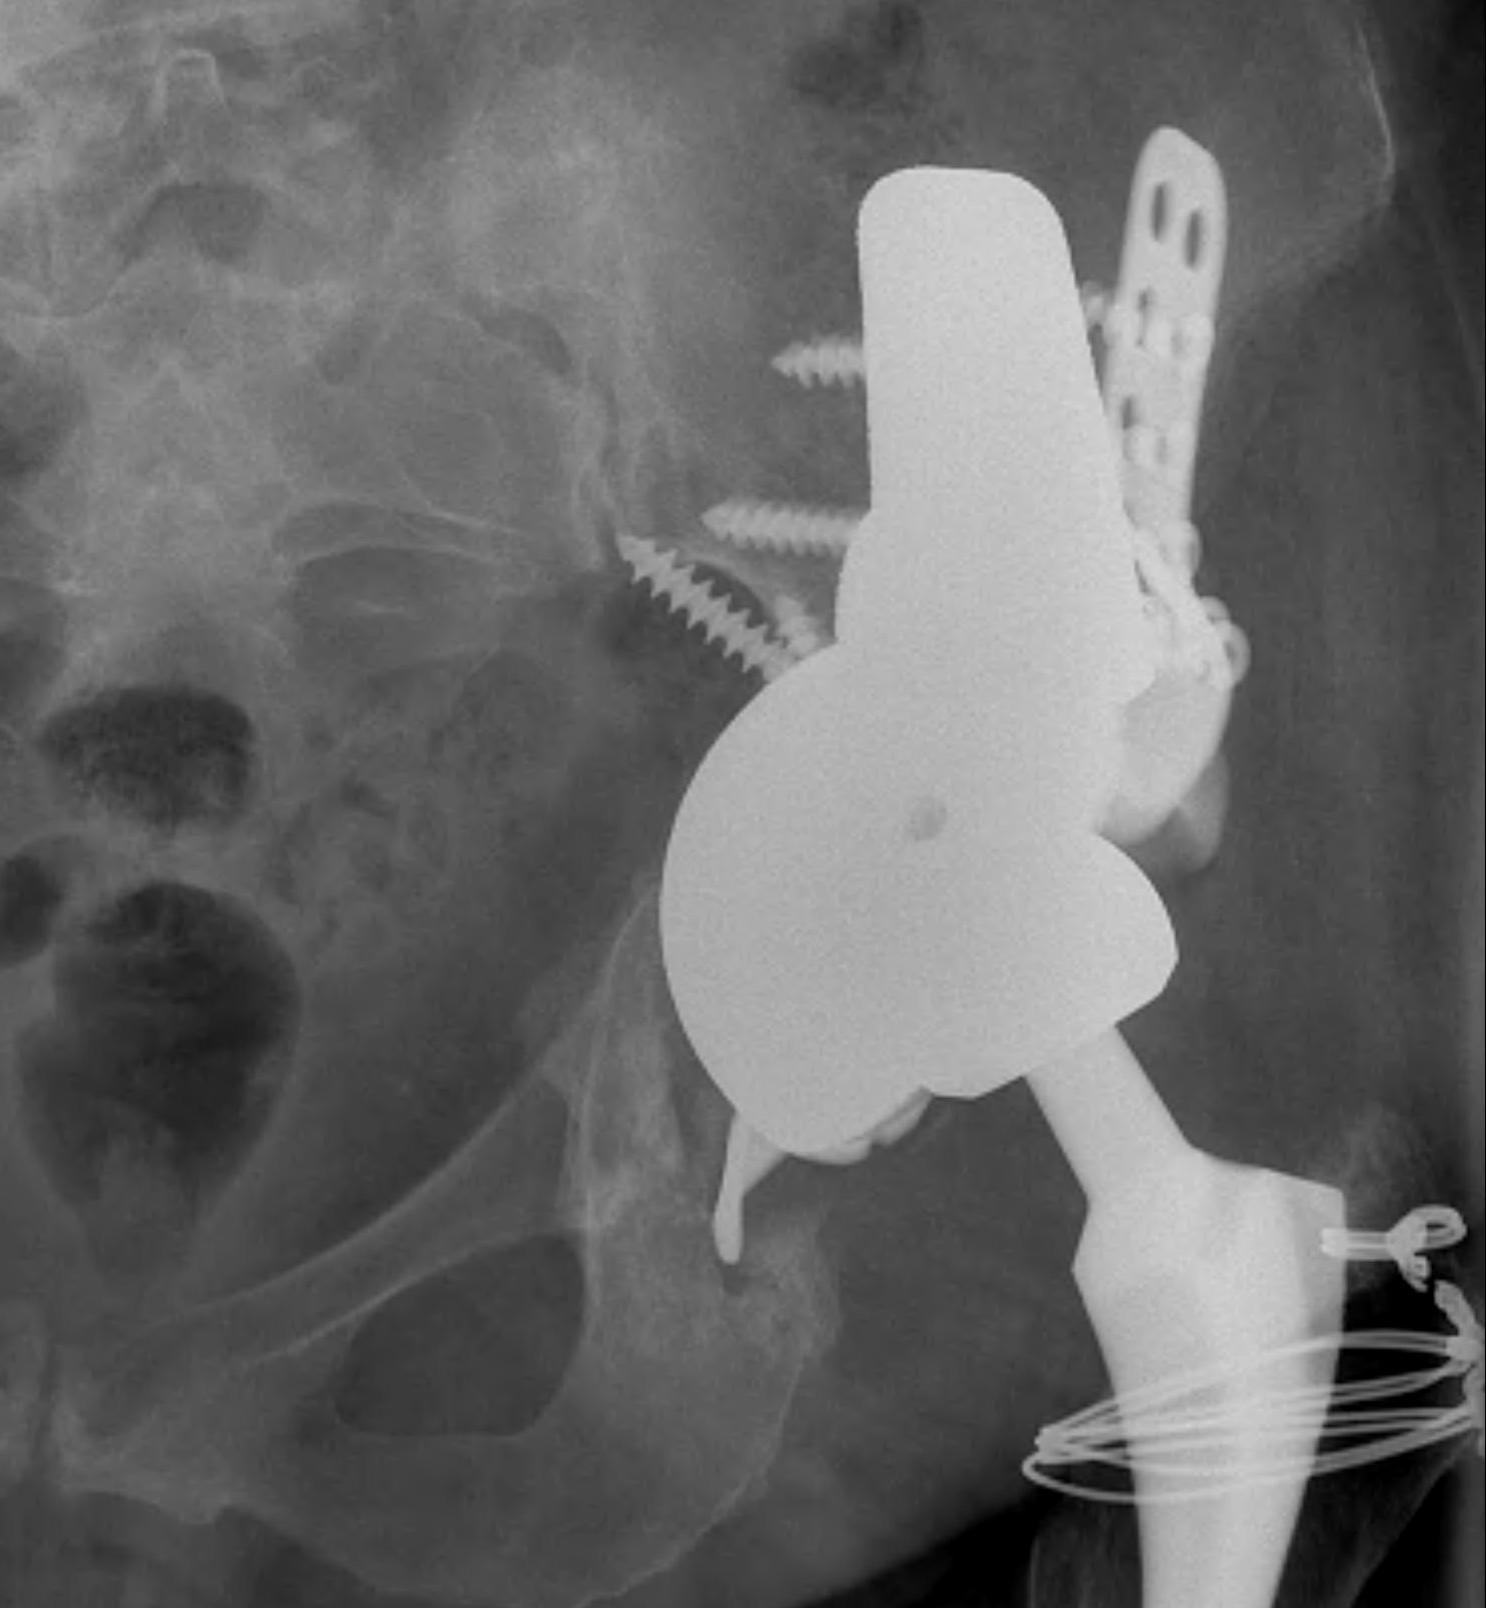

Option: Custom-made triflange components

CT guided model of pelvis

- custom made acetabular cage

- fits defect exactly

- flanges perfectly designed and not malleable to improve strength

- HA coated

- cement poly cup into it

Indications

- massive defects

Results

- 90% 4.5 year survival in complicated patients